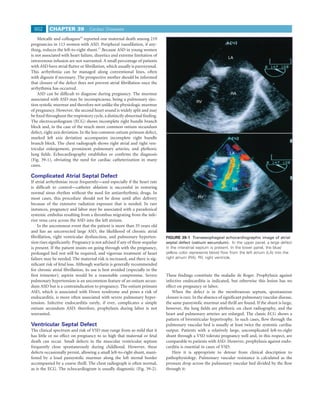

fested by a loud pansystolic murmur along the left sternal border            pathophysiology. Pulmonary vascular resistance is calculated as the

accompanied by a coarse thrill. The chest radiograph is often normal,        pressure drop across the pulmonary vascular bed divided by the flow

as is the ECG. The echocardiogram is usually diagnostic (Fig. 39-2).         through it:

FIGURE 39-2 Transesophageal echocardiographic image of a

Patent Ductus Arteriosus

small muscular ventricular septal defect. In the upper panel, a             The loud, continuous or machinery murmur of typical PDA with

small communication is seen (arrow) between the right ventricle (rv)        a large left-to-right shunt and no pulmonary vascular disease is so

and left ventricle (lv). In the lower panel, color imaging confirms blood    striking that the lesion is almost invariably detected and corrected in

flow between the two chambers. la, left atrium; ra, right atrium.            infancy or childhood. Occasionally, however, women of childbearing